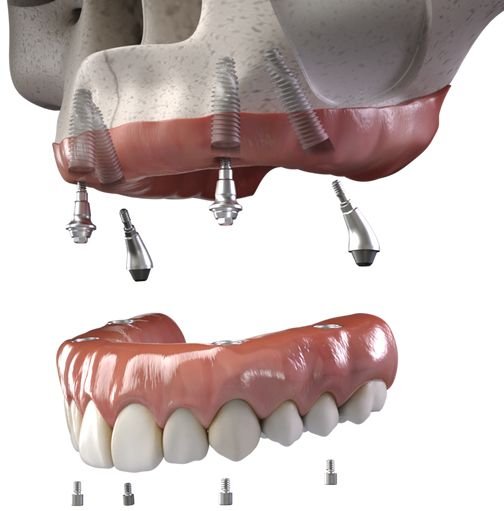

Diş İmplantları ve Restorasyonları

Sabit diş kronları (kurona), hasarlı dişi tamamen kaplayan porselen, zirkonyum veya E-max kaplamalardır;